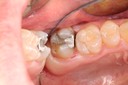

Scott Kanamori #31 prep

Scott Kanamori #31 finish